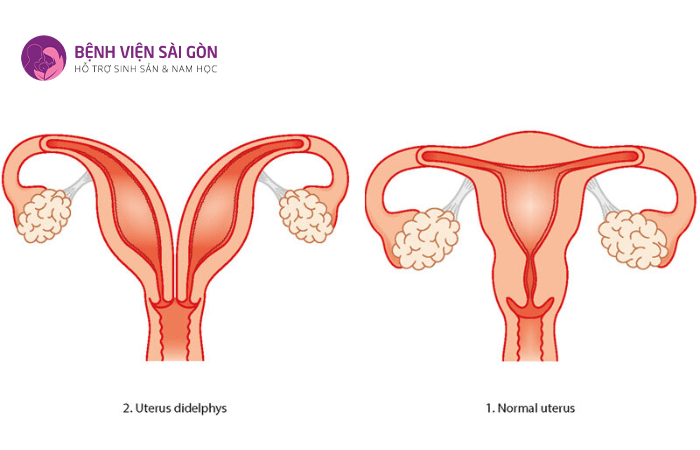

3.1 Tử cung đôi

Tử cung đôi là tình trạng có hai tử cung trong hệ thống sinh dục. Hầu hết các trường hợp, khi khám vùng chậu các bác sĩ sẽ thấy có vách ngăn dọc âm đạo hoặc xuất hiện hai cổ tử cung riêng biệt.

Nếu tình trạng này được phát hiện sớm thì tiên lượng và phát triển của thai nhi sẽ được cải thiện. Nếu chức năng của tử cung hoàn toàn bình thường thì người bệnh vẫn có thể mang thai.